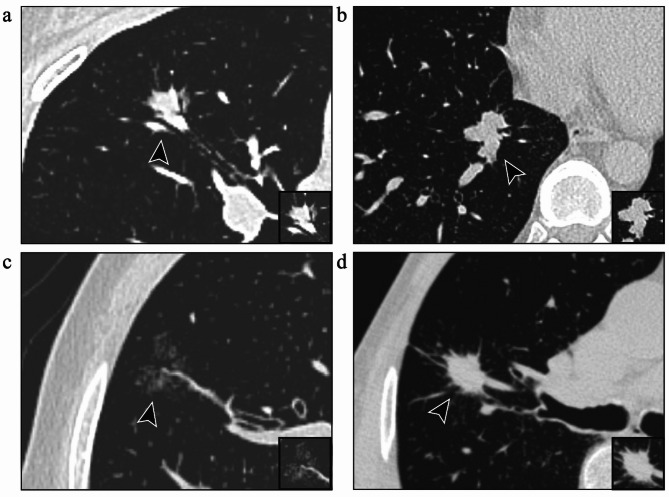

Results: Multivariate analysis identified several independent risk factors. Irregular nodule shape (OR = 1.817, 95% CI: 1.106-2.986, p = 0.018), irregular margin (OR = 2.050, 95% CI: 1.218-3.449, p = 0.007), lobulation (OR = 2.235, 95% CI: 1.336-3.739, p = 0.002), and vascular convergence (OR = 5.032, 95% CI: 2.050-12.349, p < 0.001) were significantly associated with an increased risk of STAS. Compared with a consolidation tumor ratio (CTR) = 0% (reference), a CTR of 75-100% (OR = 7.086, 95% CI: 2.542-19.750, p < 0.001) and a CTR = 100% (OR = 11.502, 95% CI: 4.752-27.840, p < 0.001) were significantly associated with an increased risk of STAS. The nomogram was developed and internally validated, demonstrating good predictive accuracy (AUC = 0.812, 95% CI: 0.761-0.863) and favorable clinical utility, with a sensitivity of 69.5% and a specificity of 80.2%.